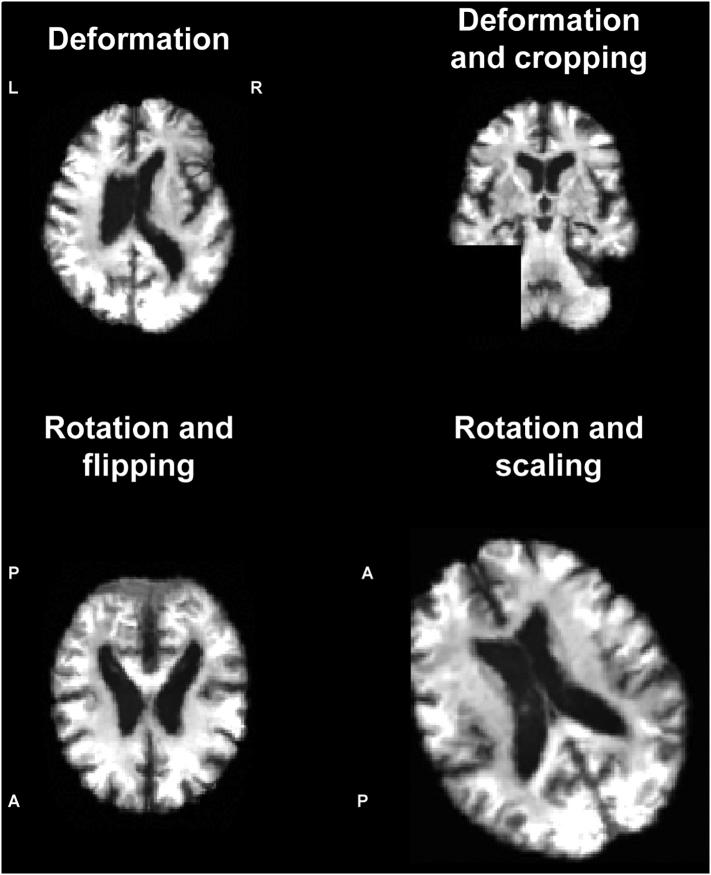

We built and validated a deep learning algorithm predicting the individual diagnosis of Alzheimer's disease (AD) and mild cognitive impairment who will convert to AD (c-MCI) based on a single cross-sectional brain structural MRI scan. Convolutional neural networks (CNNs) were applied on 3D T1-weighted images from ADNI and subjects recruited at our Institute (407 healthy controls [HC], 418 AD, 280 c-MCI, 533 stable MCI [s-MCI]). CNN performance was tested in distinguishing AD, c-MCI and s-MCI. High levels of accuracy were achieved in all the classifications, with the highest rates achieved in the AD vs HC classification tests using both the ADNI dataset only (99%) and the combined ADNI + non-ADNI dataset (98%). CNNs discriminated c-MCI from s-MCI patients with an accuracy up to 75% and no difference between ADNI and non-ADNI images. CNNs provide a powerful tool for the automatic individual patient diagnosis along the AD continuum. Our method performed well without any prior feature engineering and regardless the variability of imaging protocols and scanners, demonstrating that it is exploitable by not-trained operators and likely to be generalizable to unseen patient data. CNNs may accelerate the adoption of structural MRI in routine practice to help assessment and management of patients.